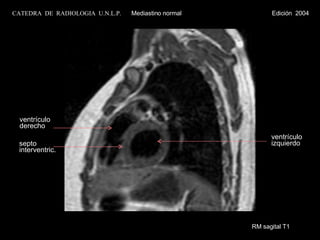

RM sagital T1ventrículo izquierdo ventrículo derecho septo interventric. CATEDRA DE RADIOLOGIA U.N.L.P. Mediastino normal Edición 2004

RM sagital T1 ventrículo  izquierdo ventrículo derecho septo  interventric. CATEDRA  DE  RADIOLOGIA  U.N.L.P.   Mediastino normal  Edición  2004